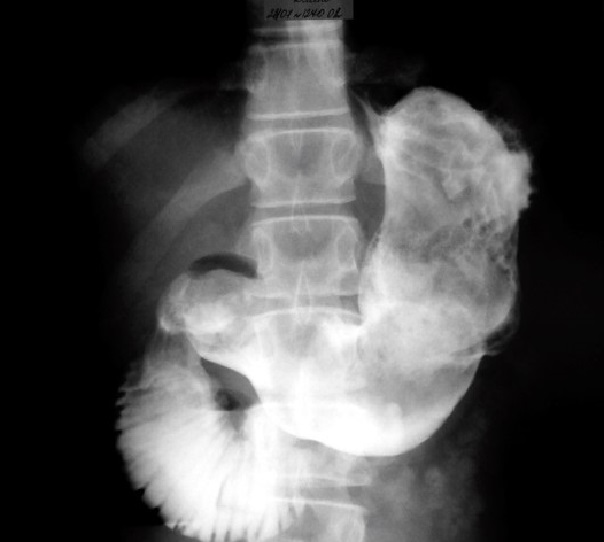

Как рассказали Life.ru в столичном Депздраве, всё началось с жалоб подростка на боль в животе. Причём других симптомов у неё не было, рвоты не наблюдалось. Во время ультразвукового исследования (УЗИ) брюшной полости в просвете желудка и двенадцатиперстной кишки было обнаружено объёмное образование. Компьютерная томография (КТ) также подтвердила наличие инородного тела. Врачи пришли к выводу, что перед ними огромный ком волос. На следующий день девочку прооперировали.

По его словам, юной пациентке необходимо было провести операцию из-за кишечной непроходимости. Трихобезоар заблокировал не только желудок, но и двенадцатиперстную кишку. Хирурги успешно удалили образование, полностью восстановив функции желудочно-кишечного тракта (ЖКТ) девочки. Пациентку уже выписали домой.